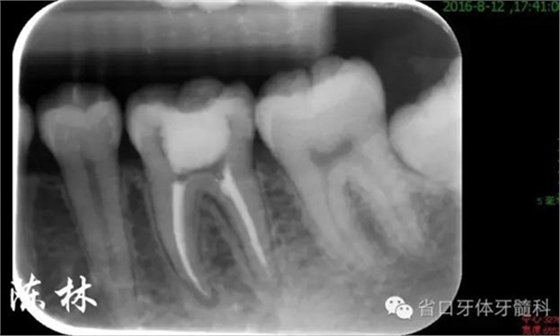

處理:36橡皮障隔離,顯微鏡下去暫封,用賽特力超聲波治療儀ET18D工作尖清理髓室,DG16探查髓底,探及3個根管口(MB、ML、D),WAVEONE鎳鈦器械根管預備(25#),1%次氯酸鈉+NS交替沖洗,超聲蕩洗,吸干,試尖。AHplus+熱牙膠連續(xù)波垂直加壓充填法充填根管,棉球ZOE暫封。根充完成片示根管適填,約1周后復診。

(圖7)根充片